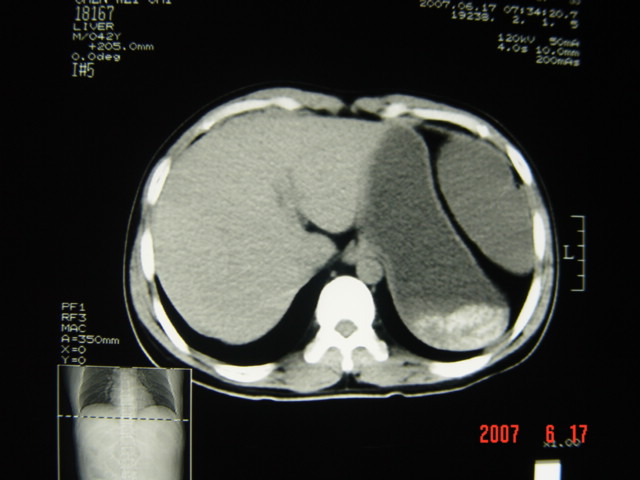

[br][br]以下是引用lkc8963在2007-6-17 13:32:00的发言:[br]完全支持邓主任意见:降/乙交界部占位性病变伴不全梗阻.做个增强或者be可能更好.